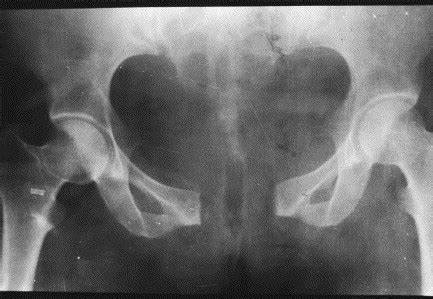

耻骨联合分离症是指骨盆前方两侧耻骨纤维软骨联合处,因外力而发生微小的错移,表现耻骨联合距离增宽或上下错动出现局部疼痛和下肢抬举困难等功能障碍的软组织损伤性疾病。

耻骨联合分离示意图

耻骨联合一般在怀孕三个月后开始变宽,统计显示,约31.7%孕妇产妇有耻骨联合处疼痛或不适,其中早孕期发生率约为12%,中孕期发生率约为34%,晚孕期高达52%。